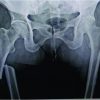

A 67-year-old female presented to the emergency department following a minor fall, reporting injury to her left lower limb. Clinical examination revealed external rotation and shortening of the left leg, with radiographs confirming a subtrochanteric fracture of left femur with features of an AFF (Fig. 1). She gave a drug history of consuming oral ibandronic acid (150 mg/month) for 7 years, as she was diagnosed with osteoporosis, indicated by a spine T-score of −3.22 on bone densitometry. In addition, the patient reported persistent right thigh pain for the preceding 3 months. Given the history of prolonged bisphosphonate use, the trivial nature of the fall, and the contralateral pain, MRI of the right femur was performed, revealing marrow edema (Fig. 2) in the subtrochanteric region, correlating with the clinical site of pain.

Recognizing the bilateral AFFs and the imminent risk of a right-sided fracture, prophylactic intramedullary nailing was performed on the right femur (Fig. 3), based on the current clinical evidence. This approach also facilitated positioning for subsequent fracture reduction and reconstruction nailing of the left femur (Fig. 4), conducted 2 days later. The postoperative course was uneventful. Bisphosphonate therapy was discontinued, and the patient was started on teriparatide injections, calcium, and vitamin D supplementation. After satisfactory post-operative X-rays (Fig. 5), full weight-bearing mobilization with walker support was initiated.